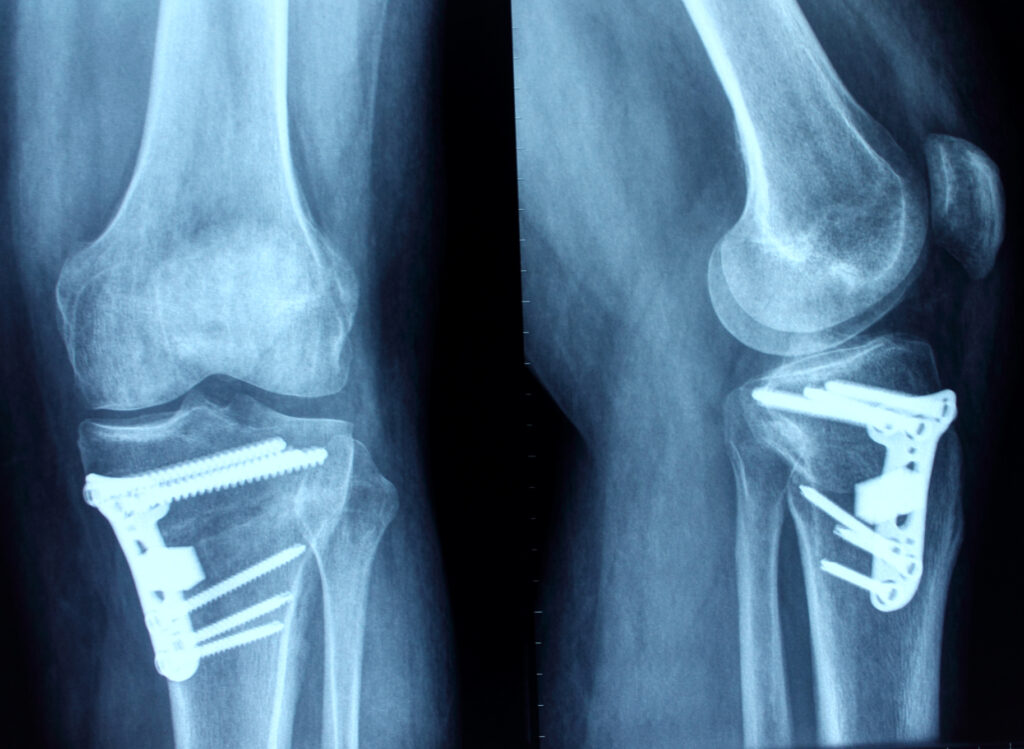

Osteotomia de tibie